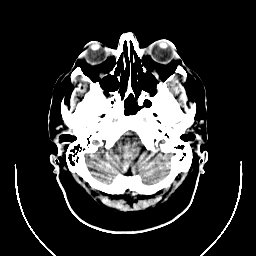

CT Study #1 -- Slice #4

[Home][Help][Clinical][Tour 1] Slice 4